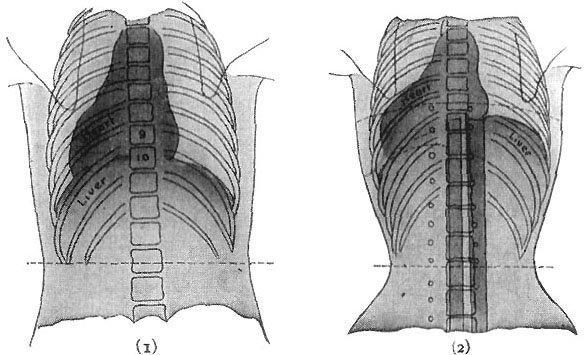

The Stomach—its Shape, Position, and Size. By means of muscular contraction, then, the gullet-elevator carries the food into the stomach. This is a comparatively simple affair, merely a ballooning out, or swelling, of the food tube, like the bulb of a syringe, making a pouch, where the food can be stored between meals, and where it can undergo a certain kind of melting or dissolving. This pouch is about the shape of a pear, with its larger end upward and pointing to the left, and its smaller end tapering down into the intestine, or bowel, on the right, just under the liver. The middle part of the stomach lies almost directly under what we call the "pit of the stomach," though far the larger part of it lies above and to the left of this point, going right up under the ribs until it almost touches the heart, the diaphragm only coming between.[3] This is one of the reasons why, when we have an attack of indigestion, and the stomach is distended with gas, we are quite likely to have palpitation and shortness of breath as well, because the gas-swollen left end of the stomach is pressing upward against the diaphragm and thus upon the heart and the lungs. Most cases of imagined heart trouble are really due to indigestion.